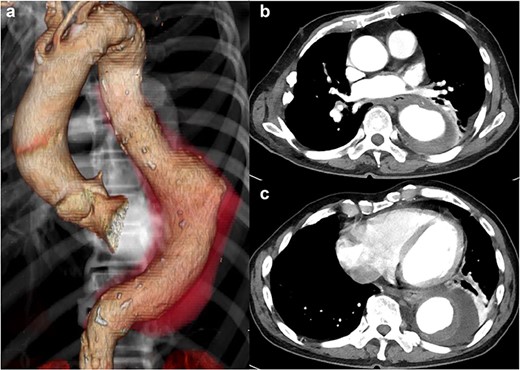

The patient had a fever (38°C) for 4 days after hospitalization, but his temperature dropped to 37°C afterward. His inflammatory reaction gradually improved, but CT angiography showed a descending aortic aneurysm, measuring 70 × 70 mm (Fig. 2). It extended 20 mm in only 2 weeks.

Preoperative CT shows acute expansion of the aneurysm to 70 mm in diameter.